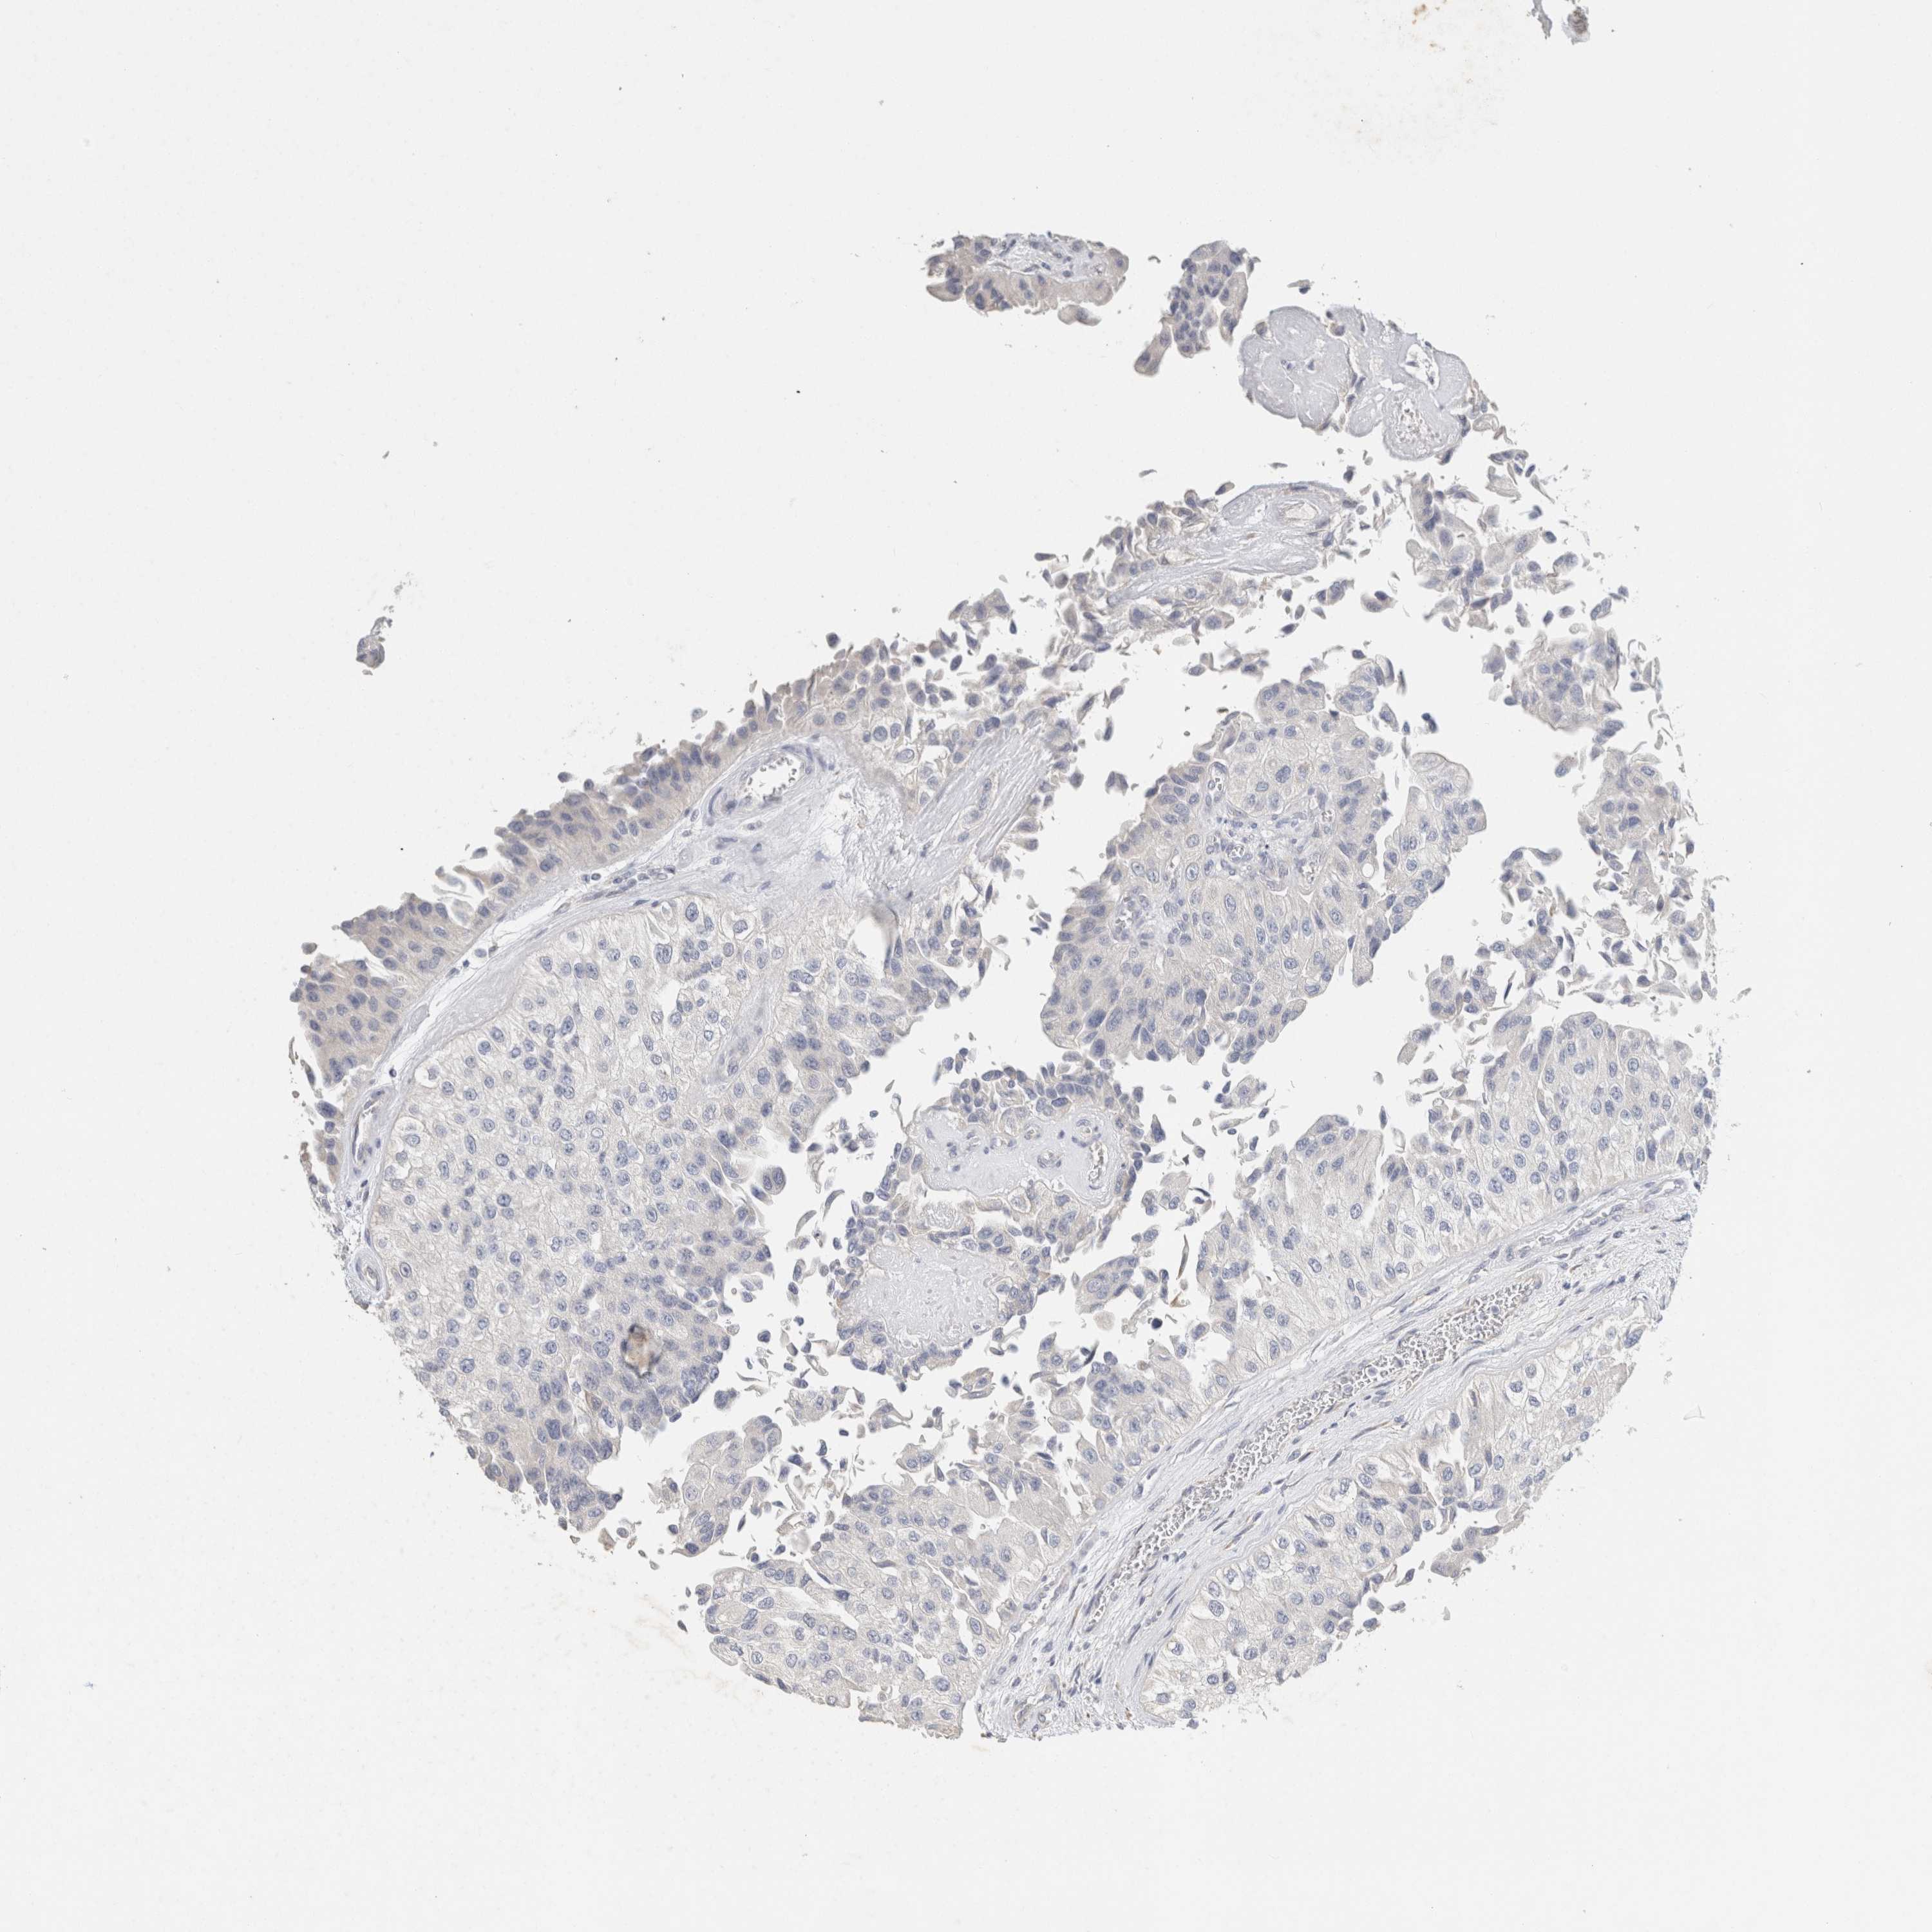

UROTHELIAL CANCER - Protein expressioni

A mouse-over function shows sample information and annotation data. Click on an image to view it in a full screen mode. Samples can be filtered based on level of antibody staining by selecting one or several of the following categories: high, medium, low and not detected. The assay and annotation is described here.

Antibody stainingi

Antibody staining in the annotated cell types in the current human tissue is reported as not detected, low, medium, or high, based on conventional immunohistochemistry profiling in selected tissues. This score is based on the combination of the staining intensity and fraction of stained cells.

Each image is clickable and will lead to virtual microscopy that enables deeper exploration of all samples and also displays staining intensity scores, fraction scores and subcellular localization as well as patient and tissue information for each sample.

Antibody HPA022845

Antibody HPA023138

Antibody CAB010900

Antibody CAB012976

Urothelial carcinoma, Low grade

Urothelial carcinoma, High grade